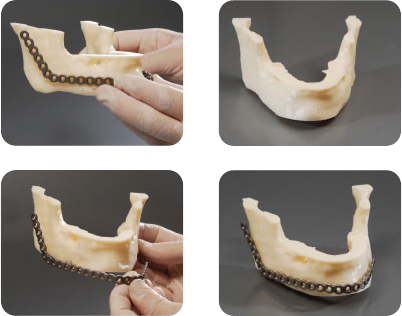

El prototipo plástico se consigue a partir de la realización de un modelado digital 3D. La pieza obtenida respeta las medidas de la anatomía, pudiendo el cirujano, de esta manera, tener una idea real de la patología a tratar.

Una vez obtenida la información de la TAC o MRI y modelado el 3D digital, podemos modelar la prótesis que se necesita (por ejemplo, una porción de calota faltante) y posteriormente realizarla en resina plástica. De esta manera validamos la adaptación del futuro implante a la anatomía. El cirujano puede verificar las imágenes modeladas digitalmente o el prototipo en resina plástica, y sugerir modificaciones dando paso al proceso final.

En otros casos el cirujano puede solicitar el modelado de alguna región anatómica con la finalidad de hacer una planificación prequirúrgica, por ejemplo, realizar en su consulta un moldeado muy exigente de placas maxilares. Luego de recibir el modelo anatómico o prototipo en resina, modela las placas que va a utilizar y las devuelve a la empresa para que sean esterilizadas antes de ser usadas, reduciendo considerablemente el tiempo quirúrgico.